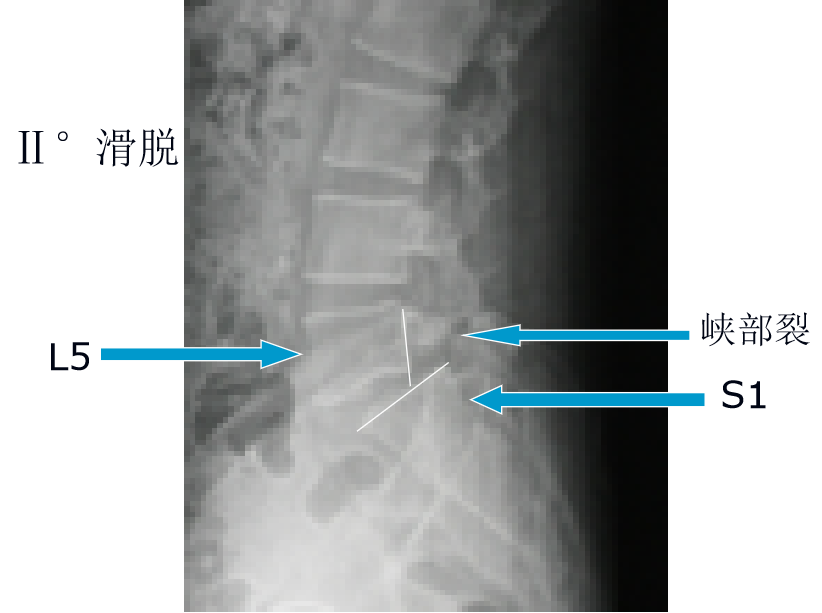

腰椎双边征

3. 双边征

滑脱椎体"双边征"椎管前后径延长,可呈"双管征".

腰5至骶1节段椎管前后径加大,滑脱的腰5椎体前移,椎体后缘形成"双边征

椎管前后径延长"双管征"滑脱椎体"双边征"(三)腰椎mri片椎弓峡部层